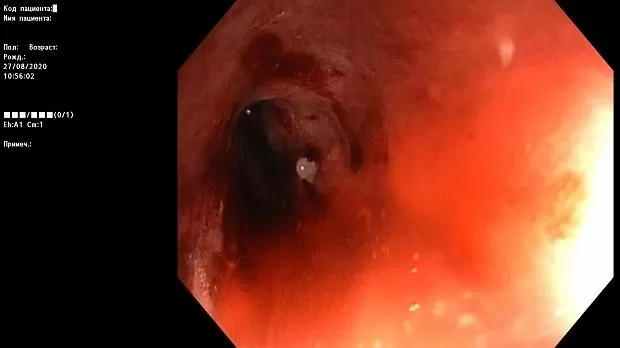

Краткое описание эндоскопической картины.

В проксимальной части сигмовидной кишки имеется асимметричное циркулярное сужение за счет плотной бугристой ткани, с признаками ригидности, структура поверхности и сосуды не визуализируются.

Просвет опухолевого канала 1 см, определенная протяженность — около 10 см. Патогистологическое исследование № 1455-62 от 28.08.2020 г.